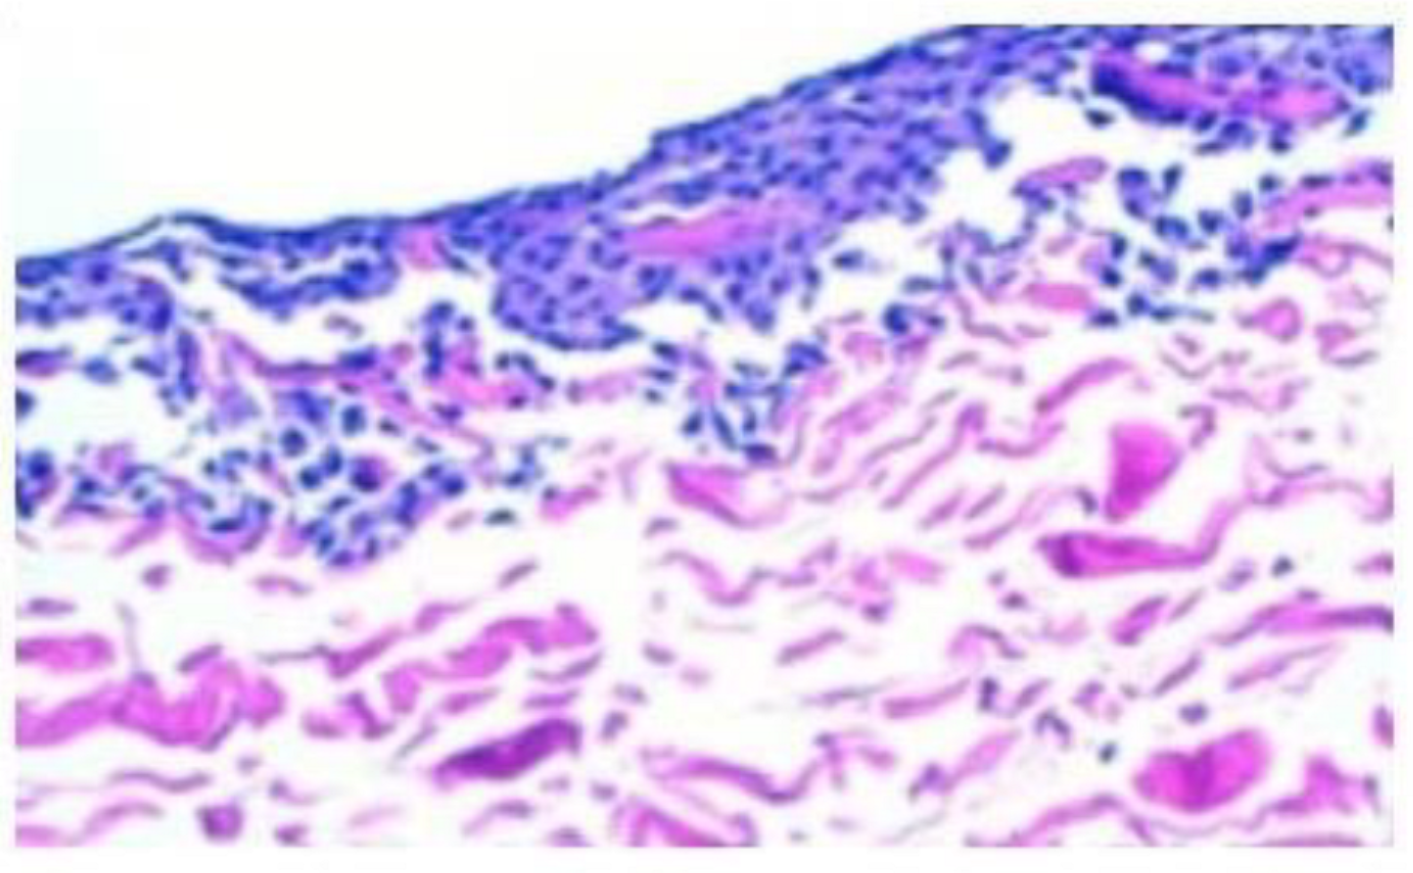

In some cases, we had to operate on some patients due to causes different to cartilage problems and when we reached the regenerated tissue, we noticed that it was softer than healthy tissue. In five cases, we could take a biopsy of the regenerated tissue two years after implantation (Figure 1). Histological analysis demonstrated the presence of scarce chondrocytes, distributed either in clusters or in columns in some areas and embedded in a hyaline matrix. We hypothesized that the reason could be that the cell density in MACI was much too low. In fact, in MACI, a total amount of 20 million cells was seeded in a 20 cm2 type I/III collagen membrane from porcine origin, so cell density was 1 million cells per cm2. For instance, if a lesion measured 3 × 2 cm, i.e., 6 cm2, a total amount of 6 million cells were implanted, with the remaining 14 million cells being wasted.

Figure 1. The histological slides stained with hematoxylin–eosin depict regenerated tissue biopsies obtained two years post membrane-assisted autologous chondrocyte implantation (MACI). The sections reveal limited chondrocytes, which are sparsely distributed either in clusters or in specific regions. These chondrocytes are found embedded within a matrix resembling hyaline cartilage. The images are captured at two different magnifications: (A) 200× magnification and (B) 400× magnification.